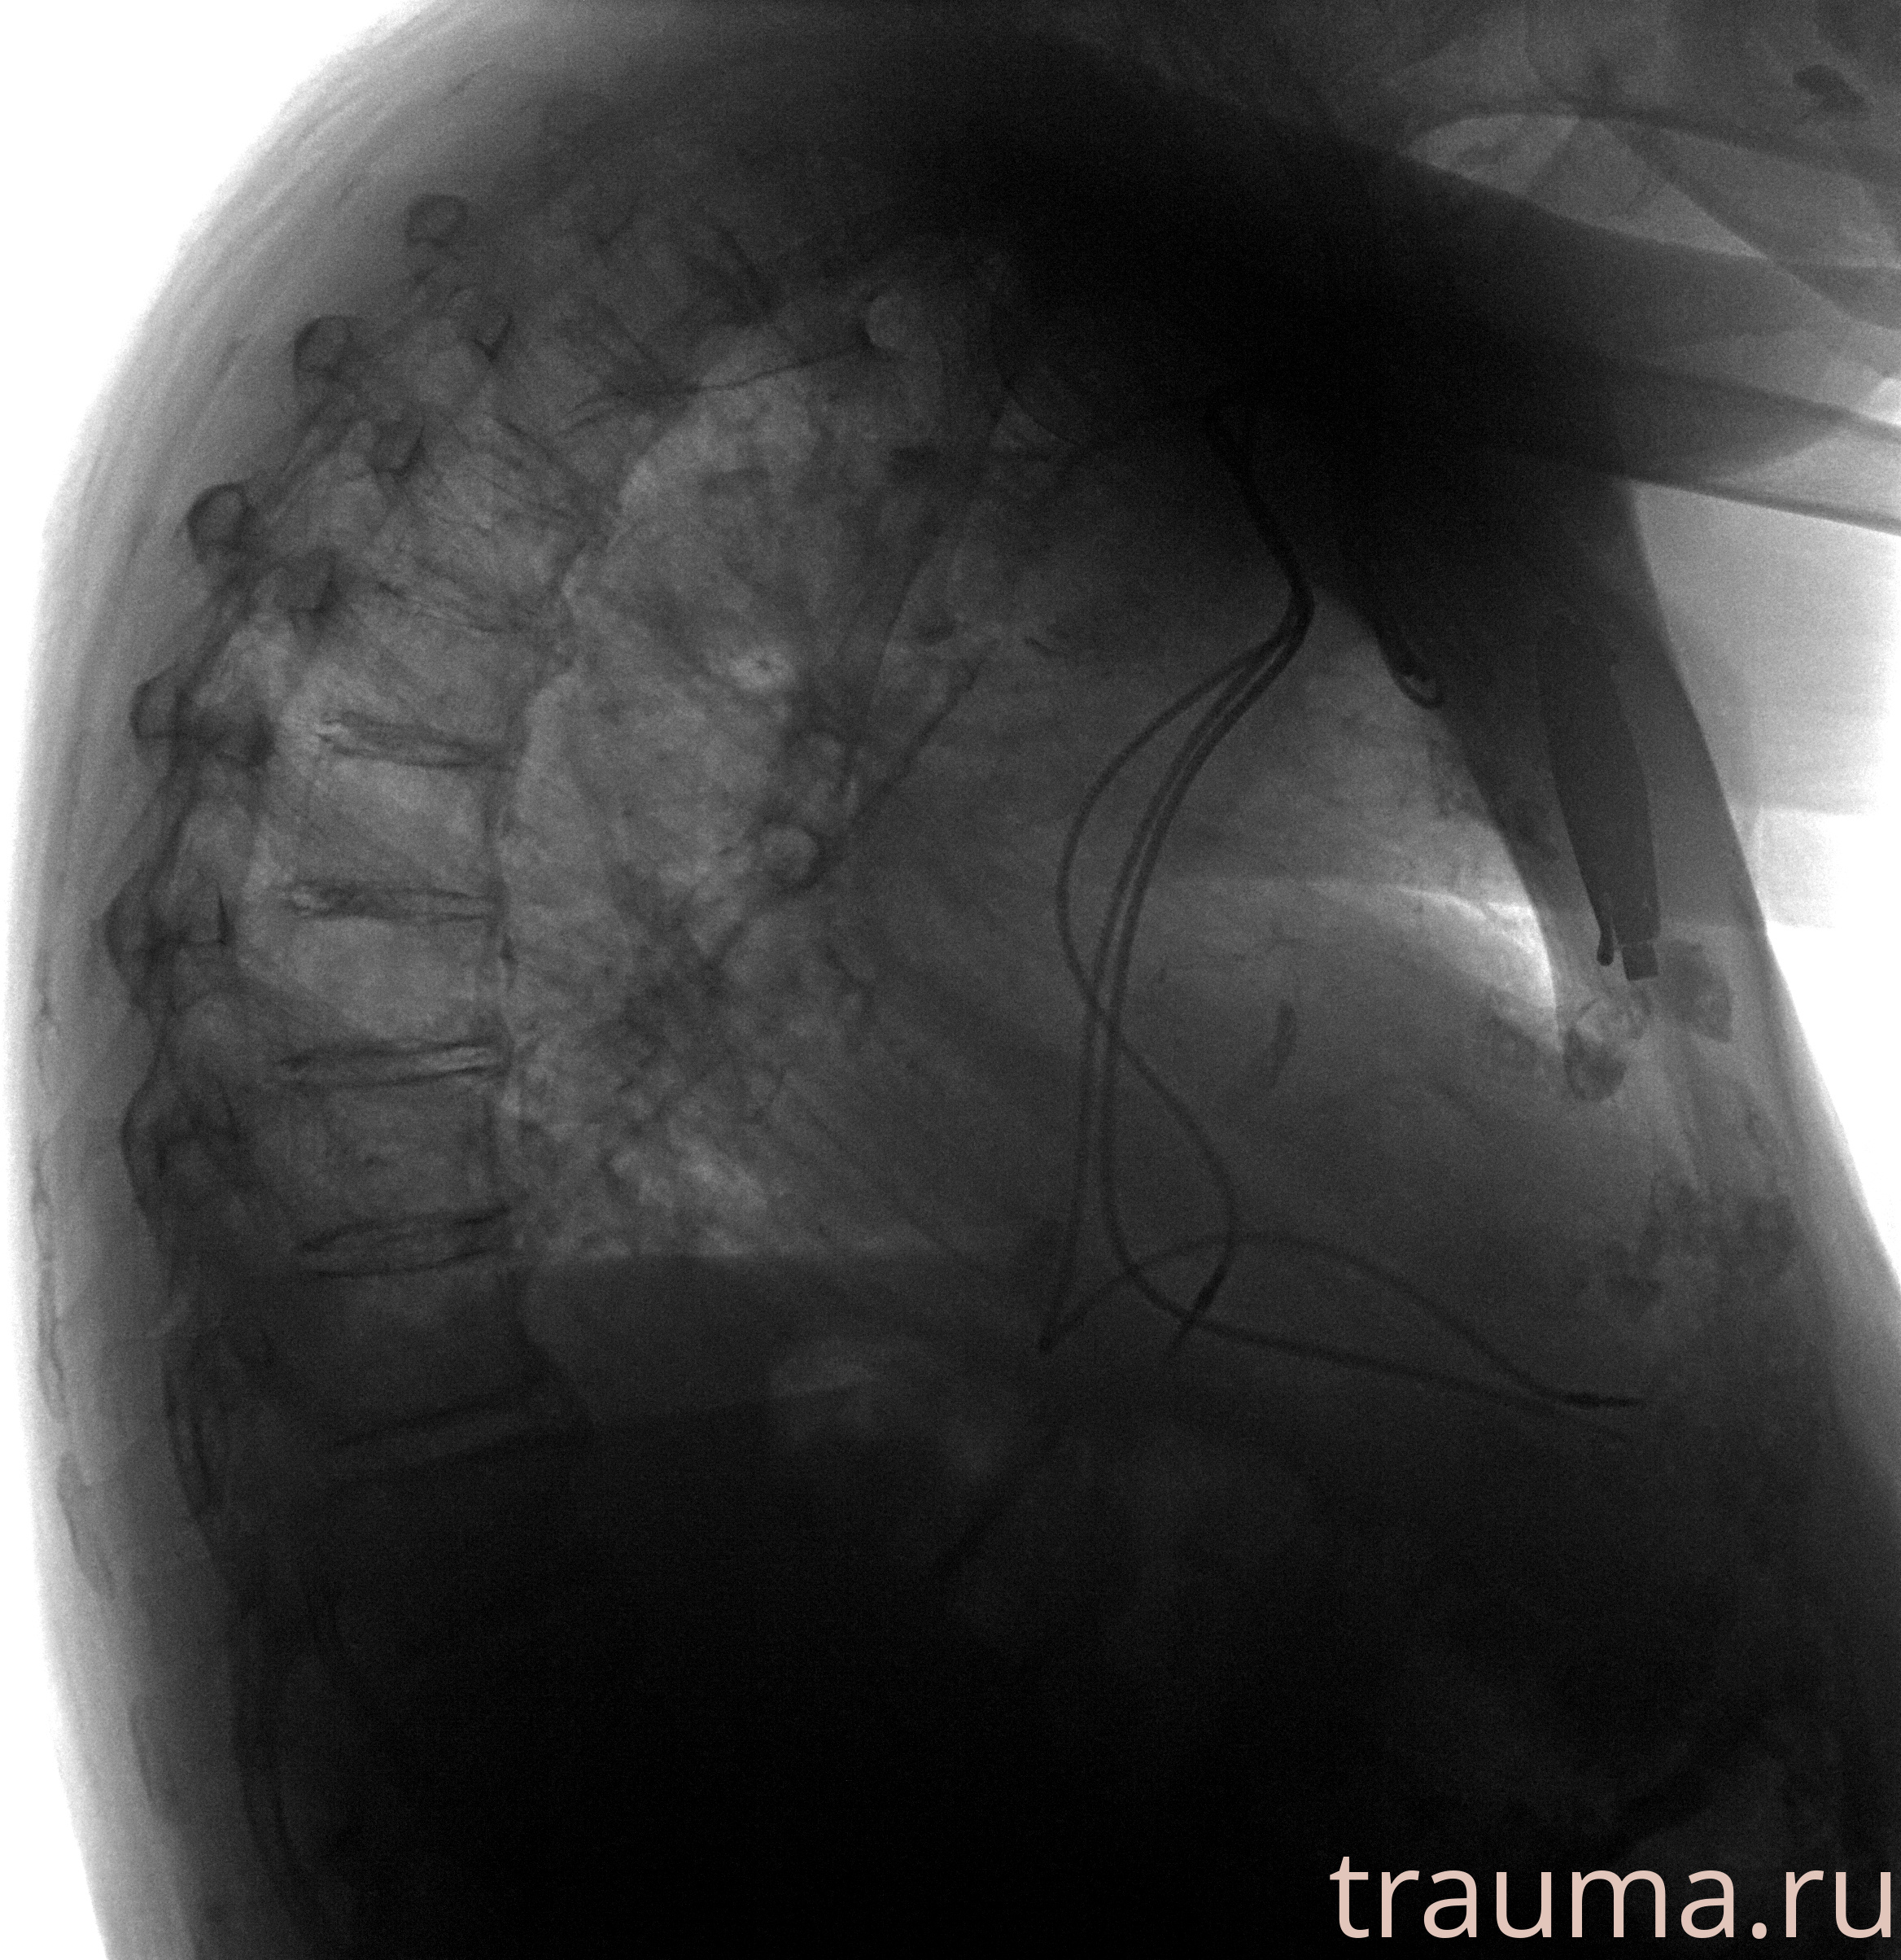

Рентгенограммы

Рентген на дому: по вашему адресу приезжает врач-рентгенолог, травматолог-ортопед с мобильным рентгеновским аппаратом, проводит диагностику травмы или заболевания, делает необходимые рентгенограммы, дает рекомендации по дальнейшему лечению. Получить качественные снимки в домашних условиях возможно благодаря уникальной методике, разработанной МосРентген Центром для института  Склифосовского